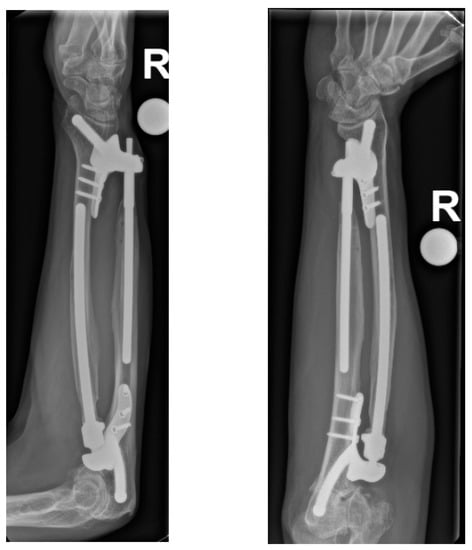

The patient we present had a motorcycle accident and underwent ex situ reconstruction of the radial head at the age of 41 with the subsequent need for a prosthesis. After the prosthesis loosened, it was removed, and an ulnar-shortening osteotomy was performed due to chronic wrist pain. Due to recurrent complaints, a Sauvé-Kapandji procedure was performed, followed by removal of the implant. The complex instability of the forearm was misunderstood throughout the course of care, up to the point when the patient presented to our clinic thirteen years after the injury. The gross instability is shown in the X-ray image of the forearm under load (Figure 1). The patient was unable to write with this hand prior to the injury dominant hand. Disabilities of Arm, Shoulder, and Hand Score was 79, grip strength on the Jamar hydraulic hand dynamometer (Performance Health Supply, Cedarburg, WI, USA) was 11 kg (44 kg on contralateral side), and pronation/supination was 10/0/10° (90/0/90° on contralateral side). The patient could only achieve a reduction in pain with low usability of the right arm through a tight cuff made of leather, which was tightly wrapped around the entire circumference of the arm and wrist every day. Without this cuff, the left hand had to support the right forearm in all positions to make movement possible.

Figure 1. A.P. and axial X-ray of the unstable forearm under load after radial head resection, failed ulna shortening osteotomy, Sauvé-Kapandji procedure, and removal of all implants.